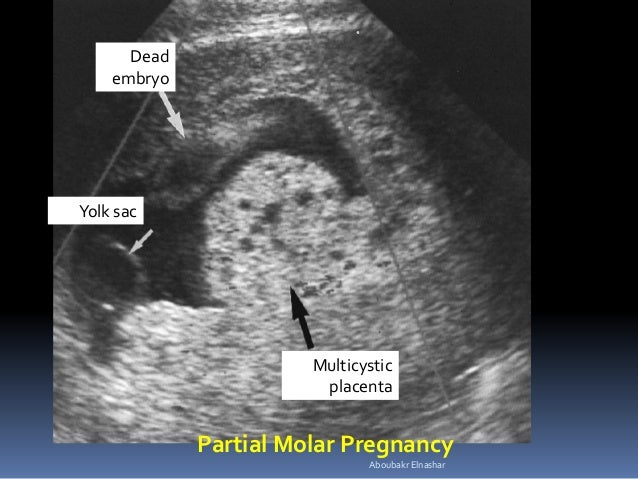

Molar Pregnancy Signs Symptoms Treatment